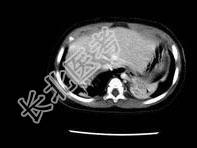

- 单项选择题男婴,11月, 咳嗽,结合图像, 最可能的诊断是 ( )

A、畸胎瘤

B、肺隔离症

C、肾母细胞瘤

D、嗜咯细胞瘤

E、神经源性肿瘤